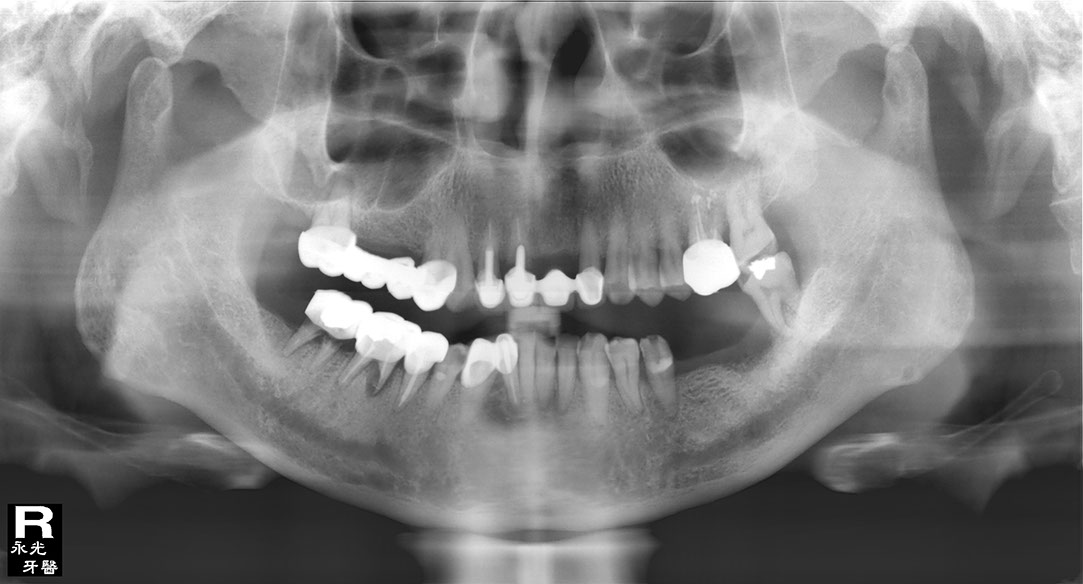

Implant 116d2.jpg

光牙醫